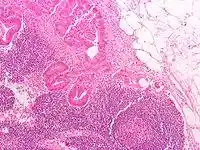

![]()

Lymph node tissue showing trabeculae

Thin reticular fibers (reticulin) of reticular connective tissue form a supporting meshwork inside the node.[2] The lymph node capsule is composed of dense irregular connective tissue with some plain collagenous fibers, and a number of membranous processes or trabeculae extend from its internal surface. The trabeculae pass inward, radiating toward the center of the node, for about one-third or one-fourth of the space between the circumference and the center of the node. In some animals they are sufficiently well-marked to divide the peripheral or cortical portion of the node into a number of compartments (nodules), but in humans this arrangement is not obvious. The larger trabeculae springing from the capsule break up into finer bands, and these interlace to form a mesh-work in the central or medullary portion of the node. These trabecular spaces formed by the interlacing trabeculae contain the proper lymph node substance or lymphoid tissue. The node pulp does not, however, completely fill the spaces, but leaves between its outer margin and the enclosing trabeculae a channel or space of uniform width throughout. This is termed the subcapsular sinus (lymph path or lymph sinus). Running across it are a number of finer trabeculae of reticular fibers, mostly covered by ramifying cells.